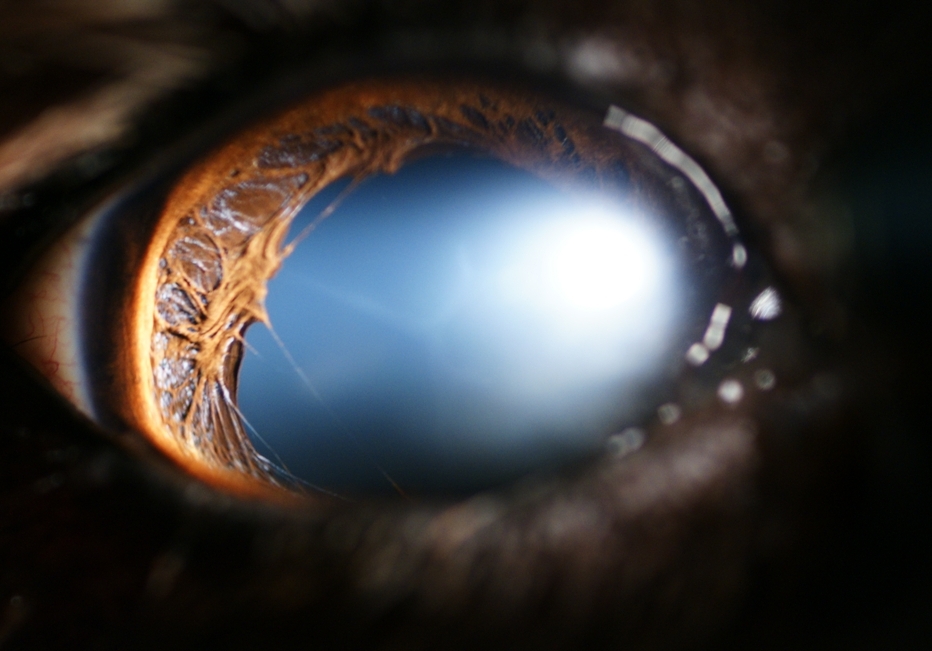

Luxation antérieure du cristallin chez un chien

- 64535 (385.82 Kio) Consulté 2728 fois